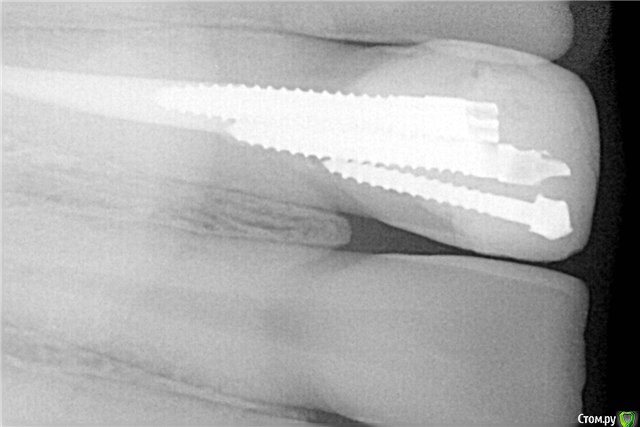

Lostikas Опубликовано 8 марта, 2019 Автор Поделиться Опубликовано 8 марта, 2019 да я сам вижу что не очень) просто я их ставлю неделя как и покашто боюсь лезть глубже из-за агресивности сверла, вы грамотно все объяснили... как я сказал раннее являюсь фанатом металических вкладок там небольшой опыт есть ~ 300-400 штифтов ни одной перфо всегда работаю как вы и написали от 1 largo до 3 largo я придерживаюсь такой философии что из нутри канала снимать по меньше тканий зуба 3 номер для себя считаю оптимальным говорю именно про апикальную треть ближе коронально может быть шире. Так вот, попробывав сверло из набора от luxapost сразу видно насколько оно агресивнее нежели старенькие подзатупившееся largo сверло. новое от luxaposta идет как по маслу и нету чувства контроля что ты на 100 % в гуте... То как вы нарисовали считаю для себя глубако слишком ослобляестся конусность зуба. возможно не прав готов выслушать ваше мнение. также слышал мнение здесь на форуме что под свш не надо заглублятся как под вкв. правда нет? Загрузите если возможно как надо) Ссылка на комментарий

Lostikas Опубликовано 8 марта, 2019 Автор Поделиться Опубликовано 8 марта, 2019 в данном случае канал 24 мм апекс 40# гутаперча, латералка+ Adseal штифт зашел на 15 мм но по факту 14мм пора в 1 мм как этого избежать(пор) Ссылка на комментарий

___49___ Опубликовано 8 марта, 2019 Поделиться Опубликовано 8 марта, 2019 старенькие подзатупившееся largo сверло выкидывайте инструмент вовремя , под анастезией можно и зуб перегреть.То как вы нарисовали считаю для себя глубако слишкомглубина ограничена необходимостью оставить состоятельной апекальную пломбу , что касаемо зуба - то для него глубже - лучше в виду более равномерного распределения нагрузки штифтом на ткани зуба.в данном случае канал 24 мм апекс 40# гутаперча, латералка+ Adseal штифт зашел на 15 мм но по факту 14мм пора в 1 мм как этого избежать(пор) пора в 1мм не так критична (при припасовке штифта в канале его не должно клинить , очень туго тоже не есть хорошо) как короткий рычаг в канале и длинный в коронковой части - см.Рис. Ссылка на комментарий

Kolchanov Опубликовано 8 марта, 2019 Поделиться Опубликовано 8 марта, 2019 Ну а что тут непонятного? Наличие полноценного феррула будет определять жизнеспособность конструкции, а не то докуда вы штифт впиндюрили. Задача штифта - дать дополнительную ретенцию пломбе. Будет у вас коронка чисто на композите висеть и никакой штифт не поможет, хоть до задницы затолкайте и крючком загните. Просто продолжите линии коронально на рисунке, где участник __49__ рекомендуемую длину заглубления штифта указал. Потеря дентина бессмысленная и беспощадная. Причем, повторюсь, совет дан абсолютно с потолка, без учета клинической ситуации. Может там вообще штамповка планируется.Я и сам любитель анкерок кинуть. Однако, если выбирать между описанной выше рекомендацией и таким вариантом, то я выберу последний. Там хоть канал не дрилили. 3 Ссылка на комментарий

___49___ Опубликовано 8 марта, 2019 Поделиться Опубликовано 8 марта, 2019 (изменено) повторюсь, совет дан абсолютно с потолкаДанный "потолок" нам преподавали ... и достаточно аргументированно объясняли смысл установки штифта на 2\3 канала с чем я согласен исходя из опыта работы на штифтах , вашу точку зрения я не совсем понял, но что касается снимков ТС и Ваших - то за период работы в хирургии, зубов где штифт был заглублен не на достаточную глубину и сломался именно в области окончания штифта - достаточно, также есть примеры когда с излишком снимают ткани внутри канала ( подбирают не "по размеру" толщину штифта к зубу) и зуб в последствии колется . ПС - и прошу еще раз обратить внимание на снимок в рекомендации - по моему беспощадной потери дентина тут нет ? и насколько мне кажется штифт нарисован с минимальным захватом стенок канала зуба ... Изменено 8 марта, 2019 пользователем ___49___ Ссылка на комментарий

Lostikas Опубликовано 9 марта, 2019 Автор Поделиться Опубликовано 9 марта, 2019 Создавая тему также считал что не стоит так сильно расверливать зуб, ведь этим самым мы сильно ослабляем его... просто в похожих ситуациях свш идет как маленькое дополнение к пломбе, усиливая всю конструкцию в целом. Согласен с Дмитрием что стоит оценить качество дентина в нутри канала перед принятием решения использывать свш. В данном случае я вообще скинул фотку ничней тройки до прерарирования, планируется мк мост, зуб бут сильно(относительно) сточен соотвесвенно соотношение коронковой части со штифтом к корневой части со штифтом будет допустимо(имхо) так зачем тогда разверливать до апекса? вы говорите 4мм пломбы какнала(гутаперчи) достаточно во ведь не будете отрицать что допустим 8 лучше? На данный момент остаетя 1 вопрос как глубако нужно заглублять свш в канал при каккой длине формируется нормальная адгезия? Вопрос к KolchanovСколько у вас занимает времени на фиксаию 1 свш? Опишите свой протокол. Спасибо! Ссылка на комментарий